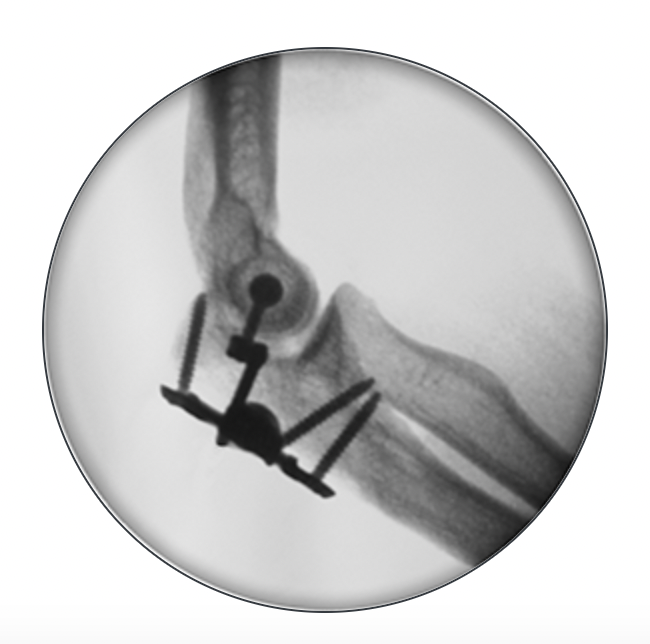

Internal joint stabilizer

IJS Elbow Stabilization System

Concept

Dynamic internal fixator

Technique

Crescenzo et al JSES Rev technique PDF

Results

- 24 patients treated with IJS-E

- 1/24 redislocated - coronoid deficient

Heifner et al J Hand Surg Glob 2023

- systematic review of 171 elbow dislocations treated with IJS-E

- implant failure 4%

- recurrent instability 4%